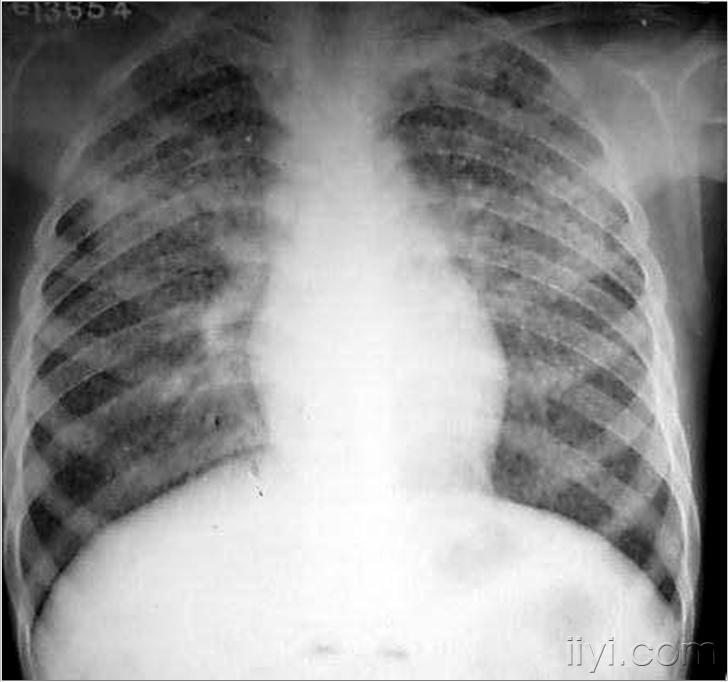

第二名患者的胸部x线片显示双肺浸润